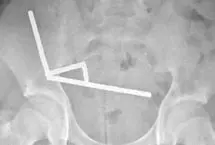

نوجوان ۱۳ سالهای در نیوزیلند پس از بلعیدن نزدیک به ۲۰۰ آهنربای قوی، دچار پارگی و انسداد روده شد و پزشکان ناچار شدند…